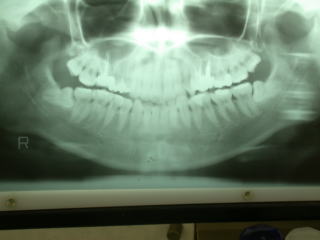

通法とおりレントゲン写真を撮影し、歯根の状態を確認します。このような場合反対側も同様な場合も多いと思われますが、右側は特に異常は認められませんでした。